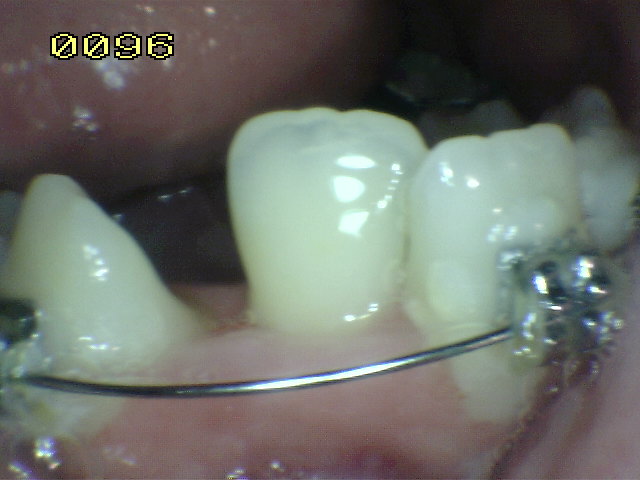

Hipoplasia de esmalte en incisivo

central |